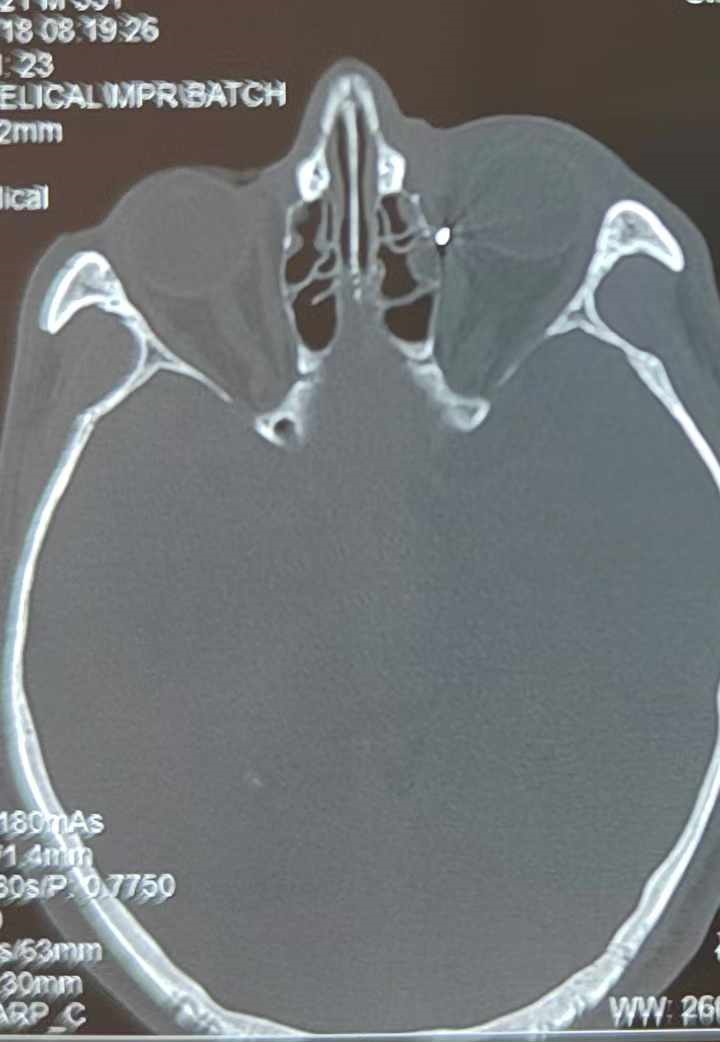

裝修工人高先生在作業(yè)過程中不慎被砸傷左眼,送至廈門眼科中心救治時,眼外傷及眼底病2科副主任醫(yī)師李海波博士在CT檢查報告中發(fā)現(xiàn),進入眼內的異物在眶尖極為隱匿的位置,想要“不動聲色”地取出來,有些難度。

從CT報告中可以看出,高先生眼內的異物不是很大,但位于眼窩深處,緊鄰鼻骨,從CT影像判斷應該是金屬或合金異物。一般臨床上遇到這樣的情況,醫(yī)生會建議“保守觀察”,若異物傷及神經(jīng)、發(fā)生炎癥感染等,則需到條件較好、有眼眶病和眼外傷專業(yè)醫(yī)師的醫(yī)院進行二期眶內異物取出術(2021年《中國眼眶異物診斷和治療專家共識》)。